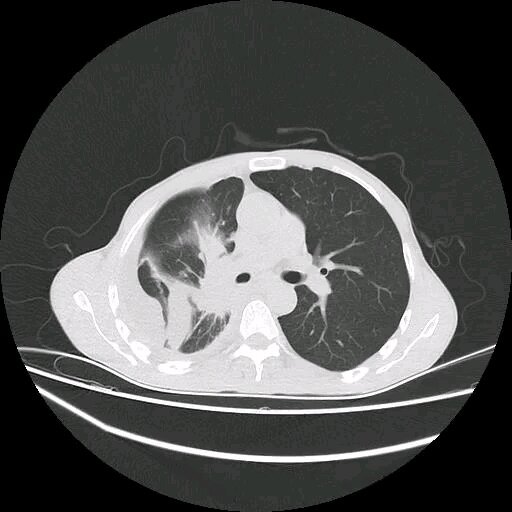

引言:當(dāng)微創(chuàng)成為可能,介入治療如何改寫抗癌戰(zhàn)場(chǎng)?“不用開胸,一根針就能消滅肺癌?”許多患者對(duì)介入治療充滿好奇,卻又因未知而恐懼。本文通過真實(shí)患者日記和全流程拆解圖,帶您親歷從入院到出院的每一步。您將看到:那些冰冷的手術(shù)器械背后,藏著怎樣精密而溫暖的生命守護(hù)。一、術(shù)前準(zhǔn)備:打有準(zhǔn)備的仗1.檢查清單:這些項(xiàng)目缺一不可必查項(xiàng)目:增強(qiáng)CT/MRI:鎖定腫瘤位置和血供(如同給癌細(xì)胞拍“高清證件照”)。凝血功能:血小板>80×10?/L,INR<1.5(防止術(shù)中“血流不止”)。肺功能測(cè)試:FEV1%>40%(確保能耐受術(shù)中體位)。避坑提示:術(shù)前4小時(shí)禁食禁水(防嘔吐誤吸)。停用阿司匹林/華法林至少5天(與醫(yī)生確認(rèn)替代方案)。2.心理建設(shè):醫(yī)生不會(huì)告訴你的“隱藏準(zhǔn)備”場(chǎng)景模擬:提前參觀介入手術(shù)室,觸摸穿刺針模型(直徑僅2mm)。疼痛管理預(yù)期:多數(shù)人痛感≤輸液扎針(視覺模擬評(píng)分VAS≤3分)。家屬任務(wù):準(zhǔn)備寬松開衫(避免術(shù)后穿衣摩擦穿刺點(diǎn))?;颊呷沼浧危骸白o(hù)士遞給我一個(gè)壓力球,說疼就捏緊。結(jié)果整個(gè)手術(shù)只用了一次——不是疼,是緊張得手抖!”二、手術(shù)當(dāng)天:60分鐘的生命重塑1.局麻穿刺:皮膚上的“蚊子叮”體位擺放:俯臥/側(cè)臥,用真空負(fù)壓墊固定(像被“溫柔包裹”)。穿刺過程:消毒鋪巾(皮膚瞬間變“手術(shù)戰(zhàn)場(chǎng)”)。局麻藥注入(刺痛感持續(xù)3秒)。穿刺針逐層突破(皮膚→皮下→胸膜→肺組織)。2.導(dǎo)管定位:血管里的“GPS導(dǎo)航”關(guān)鍵技術(shù):DSA(數(shù)字減影血管造影):實(shí)時(shí)顯示導(dǎo)管走向(如同“血管透視眼”)。超選擇性插管:將導(dǎo)管送至腫瘤供血?jiǎng)用}分支(誤差<1mm)。患者感受:體內(nèi)輕微溫?zé)岣校ㄔ煊皠┝鲃?dòng))。醫(yī)生指令:“請(qǐng)屏住呼吸10秒!”(減少肺部移動(dòng)干擾定位)。3.藥物灌注/栓塞:精準(zhǔn)投放“抗癌導(dǎo)彈”化療栓塞術(shù)(TACE):栓塞劑:載藥微球(直徑100-300μm)堵塞腫瘤血管。藥物釋放:持續(xù)15-30天(長效絞殺癌細(xì)胞)?;颊唧w驗(yàn):瞬間肝區(qū)悶脹(腫瘤缺血反應(yīng))。醫(yī)生安慰:“難受就告訴我,隨時(shí)調(diào)整速度?!被颊呷沼浧危骸案杏X像有人往肺里灌了杯溫水,有點(diǎn)脹但能忍。醫(yī)生盯著屏幕說‘腫瘤血管消失了’,我差點(diǎn)哭出來。”三、術(shù)后觀察:48小時(shí)的關(guān)鍵守護(hù)1.穿刺點(diǎn)護(hù)理:別小看這個(gè)“小傷口”沙袋壓迫2小時(shí)(防止皮下血腫)。24小時(shí)內(nèi)禁止屈腿(股動(dòng)脈穿刺者)。警示信號(hào):滲血>硬幣大小或下肢麻木(立即呼叫護(hù)士)。2.栓塞后綜合征:這些反應(yīng)很正常發(fā)熱:≤38.5℃,持續(xù)3-5天(腫瘤壞死吸收熱)。疼痛:以鈍痛為主,口服布洛芬可緩解。應(yīng)對(duì)策略:發(fā)熱期多飲水(每日>2000ml)。疼痛評(píng)分≥4分時(shí)使用嗎啡泵?;颊呷沼浧危骸巴砩习l(fā)燒到37.8℃,醫(yī)生笑著說‘癌細(xì)胞正在垂死掙扎’。原來發(fā)燒也可以是好事!”四、出院標(biāo)準(zhǔn):達(dá)到這些指標(biāo)才能回家評(píng)估項(xiàng)目達(dá)標(biāo)要求常見問題處理穿刺點(diǎn)無滲血、血腫延遲拔管+加壓包扎體溫<37.5℃超過24小時(shí)物理降溫+萘普生口服活動(dòng)能力獨(dú)立行走>50米床邊坐起訓(xùn)練+家屬攙扶實(shí)驗(yàn)室檢查血常規(guī)/肝腎功能無惡化靜脈營養(yǎng)支持+保肝治療五、患者日記:72小時(shí)全記錄時(shí)間軸:術(shù)前1天:“隔壁床阿姨剛做完回來,說像睡了一覺??晌叶⒅旎ò鍞?shù)羊到凌晨3點(diǎn)...”術(shù)中:“聽到機(jī)器滴滴聲,醫(yī)生突然說‘找到腫瘤老巢了!’原來我的癌細(xì)胞藏在右肺下葉背段...”術(shù)后6小時(shí):“右胸有點(diǎn)悶,但看著監(jiān)護(hù)儀上平穩(wěn)的數(shù)字,終于吃了口粥——真香!”出院當(dāng)天:“護(hù)士小姐姐撕下敷貼,針眼小到幾乎看不見??拱?,原來可以不那么慘烈?!绷?、專家忠告:這些細(xì)節(jié)決定成敗術(shù)后1個(gè)月:避免提重物>5kg(防穿刺點(diǎn)遲發(fā)性出血)。復(fù)查腫瘤標(biāo)志物+增強(qiáng)CT(評(píng)估壞死率)。長期管理:介入治療非一勞永逸,需聯(lián)合靶向/免疫治療。戒煙并安裝空氣凈化器(降低二次癌變風(fēng)險(xiǎn))。結(jié)語:微創(chuàng)時(shí)代的生命禮贊從恐懼顫抖到微笑出院,介入治療用毫米級(jí)的精準(zhǔn),詮釋了現(xiàn)代醫(yī)學(xué)的溫度。這根細(xì)針穿刺的不僅是腫瘤,更是擊潰絕望的希望之光。記住,抗癌路上——?jiǎng)?chuàng)傷小≠效果弱,微創(chuàng)也能創(chuàng)造生命奇跡!下期預(yù)告:《肺癌介入治療三大風(fēng)險(xiǎn)!這些信號(hào)要警惕》

引言:找到你的“抗癌武器庫”?“同樣是肺癌,為什么他能做介入治療,我卻不能?”這是許多患者和家屬的困惑。介入治療雖好,但并非人人適用。本文將用一張清晰的自測(cè)流程圖,帶您快速判斷是否屬于“介入治療候選人群”,同時(shí)揭秘哪些情況必須繞道而行。??一、介入治療的“黃金名單”:這4類患者優(yōu)先考慮?1.早期肺癌:無法手術(shù)者的“PlanB”?適用條件:?腫瘤大?。褐睆健?cm(約一顆葡萄大?。?。?腫瘤位置:位于肺外周1/3區(qū)域(遠(yuǎn)離主支氣管和大血管)。?身體狀況:因高齡(>75歲)、心肺功能差或合并其他疾?。ㄈ鐕?yán)重心臟?。o法耐受手術(shù)。案例故事:72歲的張爺爺,因慢性肺氣腫無法手術(shù),經(jīng)射頻消融治療后,腫瘤完全壞死,隨訪2年無復(fù)發(fā)。?2.中晚期肺癌:腫瘤太大?先“縮瘤”再根治!?適用場(chǎng)景:?局部晚期:腫瘤侵犯胸膜或淋巴結(jié),但尚未遠(yuǎn)處轉(zhuǎn)移。?腫瘤負(fù)荷大:通過介入栓塞或灌注化療縮小腫瘤,為手術(shù)或放療爭(zhēng)取機(jī)會(huì)。?癥狀控制:如腫瘤壓迫導(dǎo)致咯血、呼吸困難,介入可快速止血、緩解壓迫。數(shù)據(jù)支持:研究顯示,中晚期肺癌經(jīng)介入聯(lián)合免疫治療后,手術(shù)切除率從15%提升至40%!?3.心肺功能差:微創(chuàng)治療“保命不傷身”?典型人群:?慢阻肺(COPD)患者:肺功能檢測(cè)FEV1(一秒量)<50%。?心臟病患者:如嚴(yán)重冠心病、心力衰竭,無法承受全麻手術(shù)風(fēng)險(xiǎn)。醫(yī)生提醒:介入治療采用局部麻醉,對(duì)心肺功能要求低,術(shù)后無需插管,呼吸衰竭風(fēng)險(xiǎn)大幅降低。?4.多發(fā)病灶或術(shù)后復(fù)發(fā):精準(zhǔn)打擊“游擊戰(zhàn)”?適用情況:?多原發(fā)肺癌:雙肺散布多個(gè)小腫瘤(≤3個(gè))。?術(shù)后局部復(fù)發(fā):避免二次開胸創(chuàng)傷。技術(shù)優(yōu)勢(shì):一次治療可同時(shí)處理多個(gè)病灶,且對(duì)剩余肺功能影響極小。?二、介入治療的“禁區(qū)”:這5類患者需謹(jǐn)慎?1.腫瘤位置太“刁鉆”??危險(xiǎn)區(qū)域:緊貼主支氣管、大血管或心臟。?風(fēng)險(xiǎn)提示:熱消融可能損傷重要結(jié)構(gòu),導(dǎo)致大出血或氣道瘺。替代方案:可選擇冷凍消融(氬氦刀)或納米刀,或者粒子植入,降低熱損傷風(fēng)險(xiǎn)。?2.全身廣泛轉(zhuǎn)移判斷標(biāo)準(zhǔn):轉(zhuǎn)移灶≥3個(gè)器官(如肝、骨、腦)。ECOG體能評(píng)分≥3分(生活無法自理)。醫(yī)生建議:此時(shí)以全身治療(靶向、免疫)或姑息治療為主,介入僅用于緩解急癥(如大咯血)。?3.凝血功能嚴(yán)重異常禁忌指標(biāo):血小板<50×10?/L。INR(凝血酶原時(shí)間)>1.5。應(yīng)對(duì)策略:輸注血小板或新鮮血漿糾正凝血功能后,仍可考慮介入治療。?4.全身感染或膿毒血癥風(fēng)險(xiǎn)預(yù)警:介入穿刺可能將感染擴(kuò)散至胸腔,引發(fā)膿胸或敗血癥。?5.預(yù)期生存期<3個(gè)月醫(yī)生忠告:過度治療可能加重痛苦,此時(shí)應(yīng)優(yōu)先考慮舒緩療護(hù)。?三、自測(cè)流程圖:3分鐘判斷你是否適合步驟1:看腫瘤分期早期(Ⅰ-Ⅱ期)→進(jìn)入步驟2。中晚期(Ⅲ-Ⅳ期)→需結(jié)合轉(zhuǎn)移情況(見步驟4)。步驟2:評(píng)估手術(shù)耐受性心肺功能差/高齡/合并癥多→適合介入。身體條件良好→優(yōu)先手術(shù)。步驟3:檢查腫瘤位置與大小外周+≤3cm→適合消融。中央型/>5cm→考慮動(dòng)脈灌注或栓塞。步驟4:排查轉(zhuǎn)移與全身狀態(tài)孤立轉(zhuǎn)移灶→可聯(lián)合介入+全身治療。廣泛轉(zhuǎn)移+體能差→建議保守治療。?四、患者必讀:這些檢查幫你鎖定答案1.增強(qiáng)CT/MRI:明確腫瘤大小、位置及與血管關(guān)系。2.肺功能檢查:FEV1%預(yù)測(cè)值決定能否耐受手術(shù)。3.凝血四項(xiàng)+血常規(guī):排除出血風(fēng)險(xiǎn)。4.PET-CT:發(fā)現(xiàn)潛在轉(zhuǎn)移灶,避免盲目治療。?五、專家答疑:高頻問題一站式解答Q1:我腫瘤4cm,但有糖尿病,能做介入嗎?→可以!糖尿病不是禁忌癥,術(shù)前需控制血糖至<10mmol/L。Q2:介入治療后還能做手術(shù)嗎?→完全可以!介入可縮小腫瘤,為手術(shù)創(chuàng)造更好條件。Q3:多發(fā)結(jié)節(jié)必須全部處理嗎?→優(yōu)先處理主病灶,<1cm的亞厘米結(jié)節(jié)可定期觀察。?六、結(jié)語:適合自己的才是最好的介入治療不是“萬能鑰匙”,也非“最后稻草”。通過本文的自測(cè)流程圖和詳細(xì)解讀,您已初步掌握選擇依據(jù)。但最終方案務(wù)必由多學(xué)科團(tuán)隊(duì)(MDT)綜合評(píng)估!抗癌是場(chǎng)“精準(zhǔn)戰(zhàn)役”,選對(duì)武器,方能事半功倍。下期預(yù)告:《介入治療能徹底消滅肺癌嗎?醫(yī)生說出大實(shí)話!》——根治還是姑息?